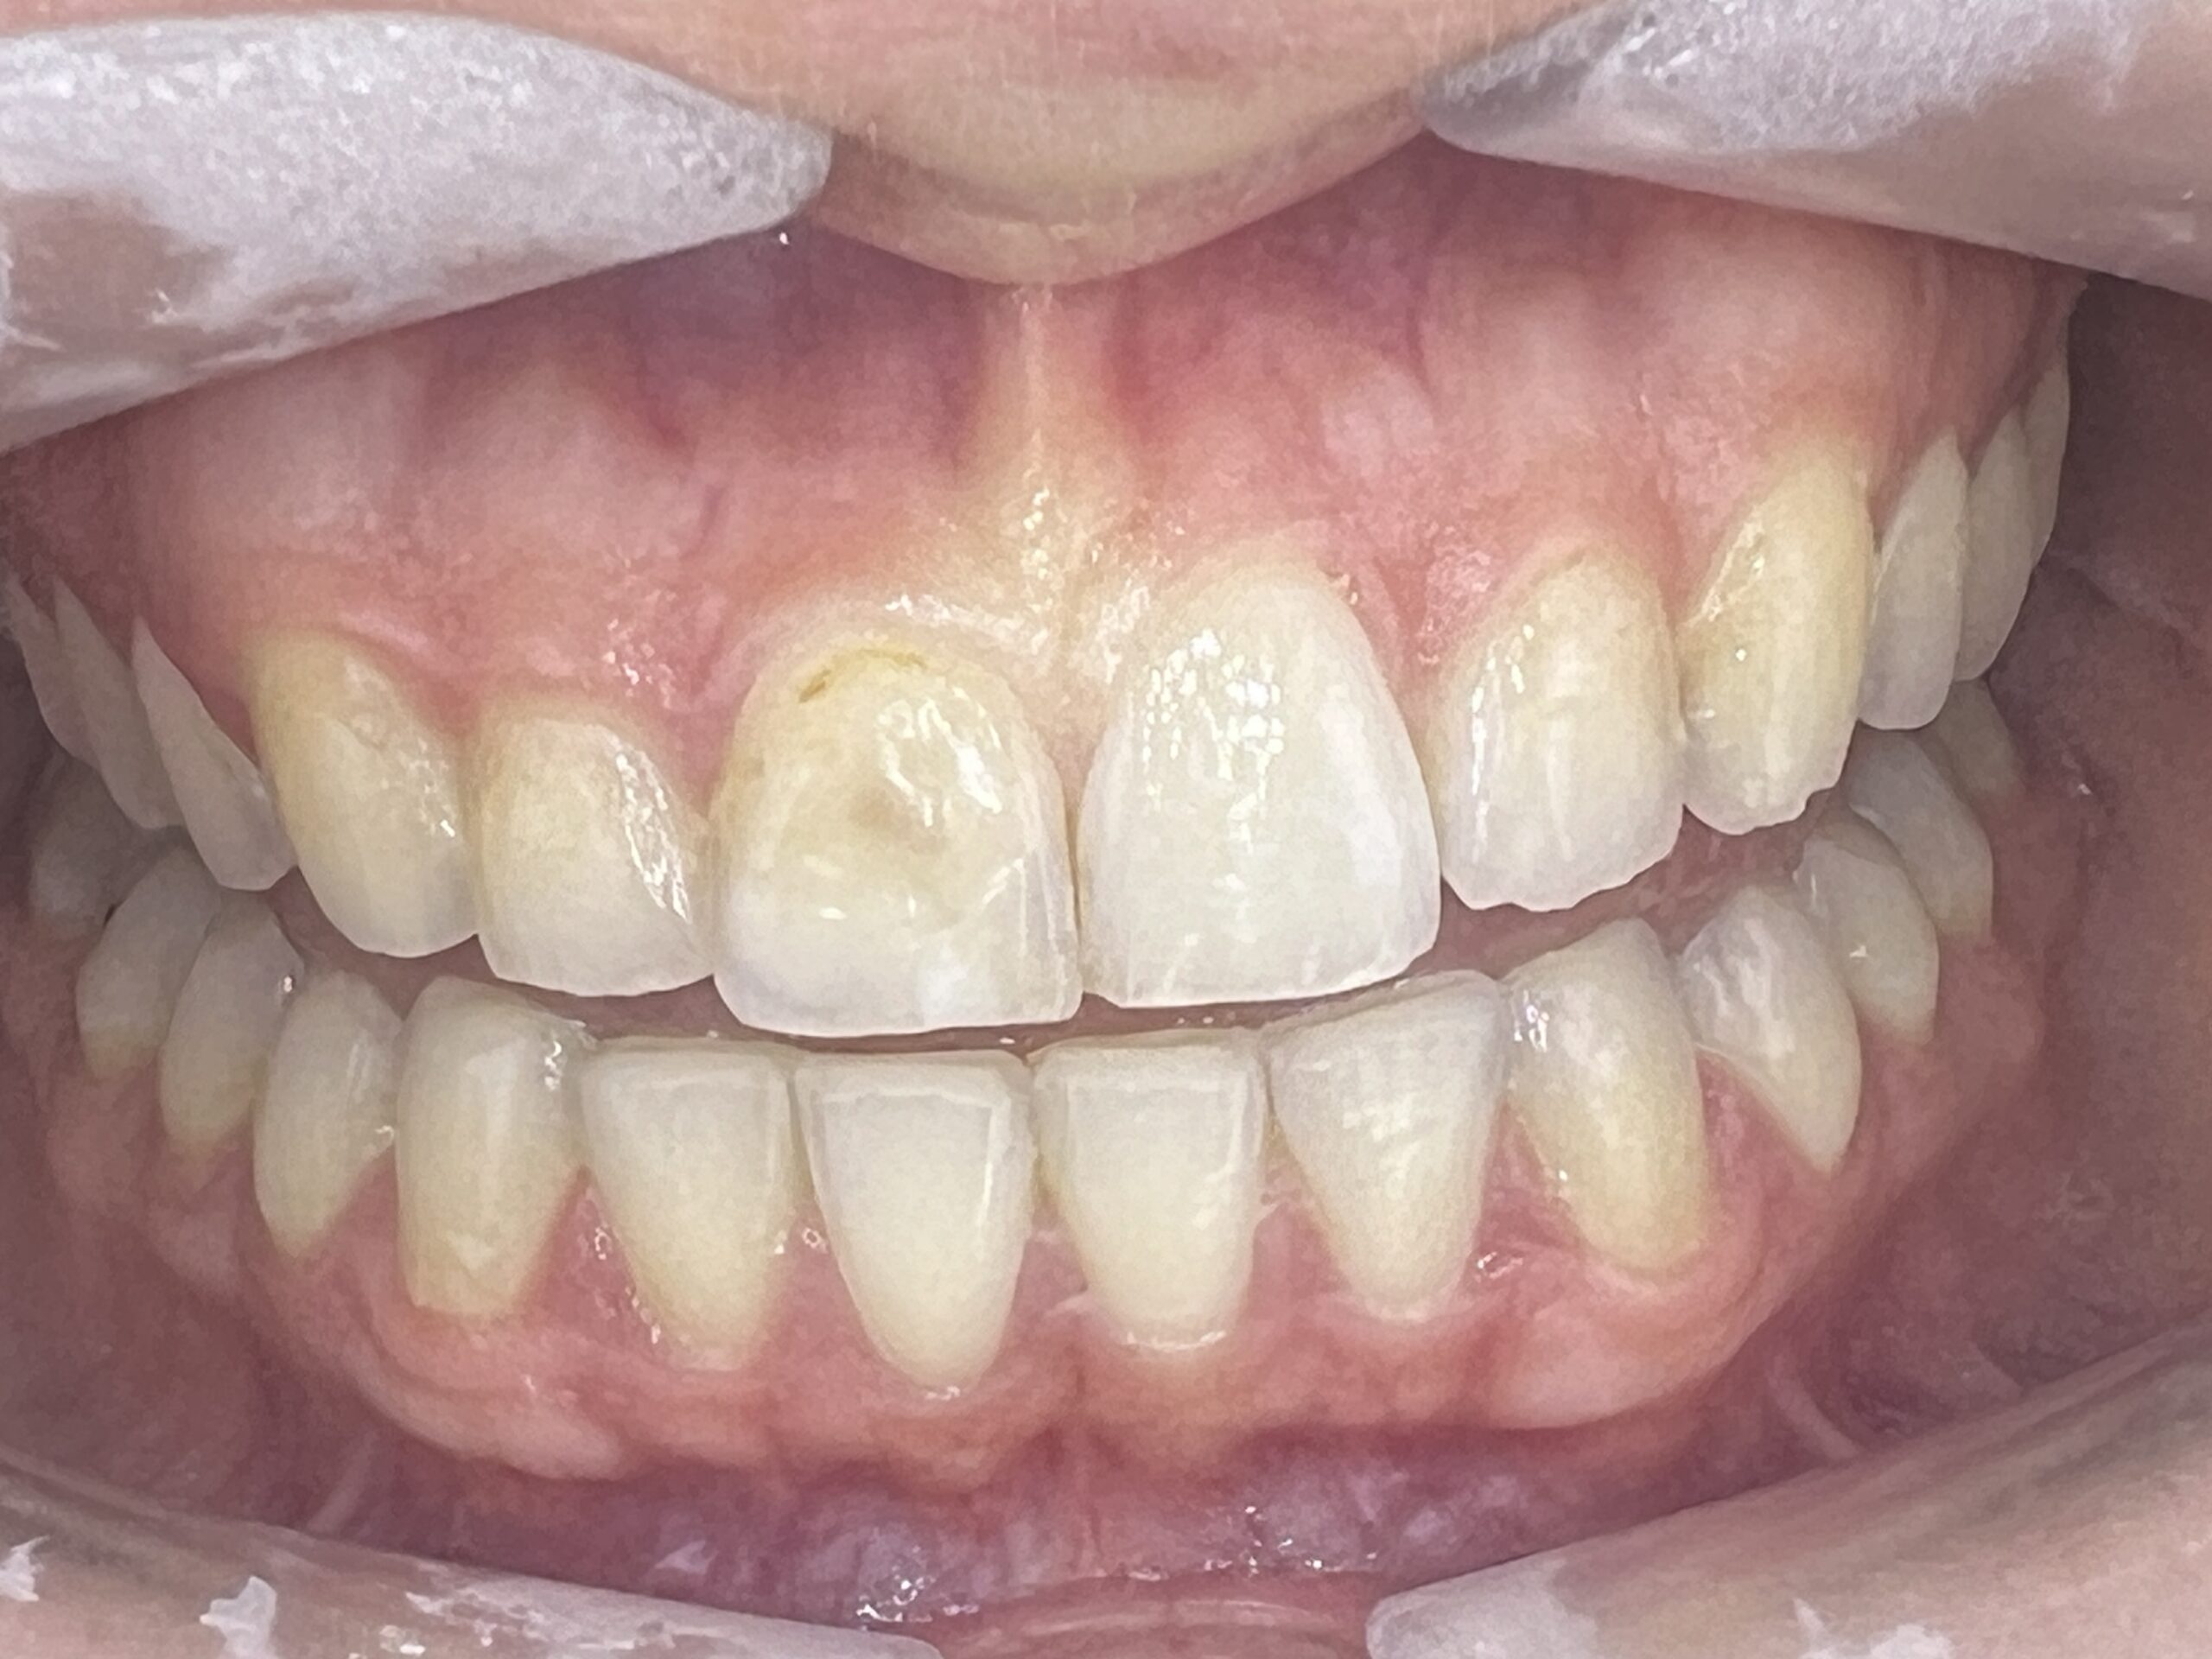

Clinical situation before

Clinical situation after. Natural shade